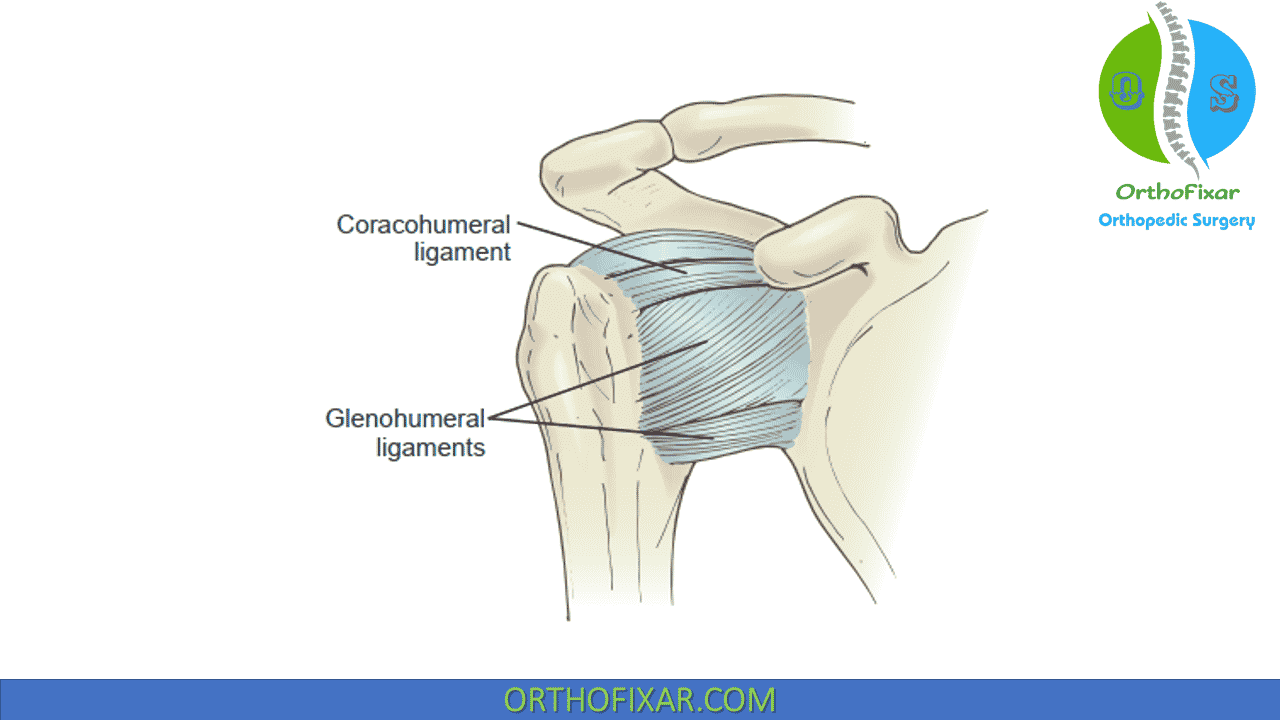

Glenohumeral ligament: анатомия и функции плечевого сустава